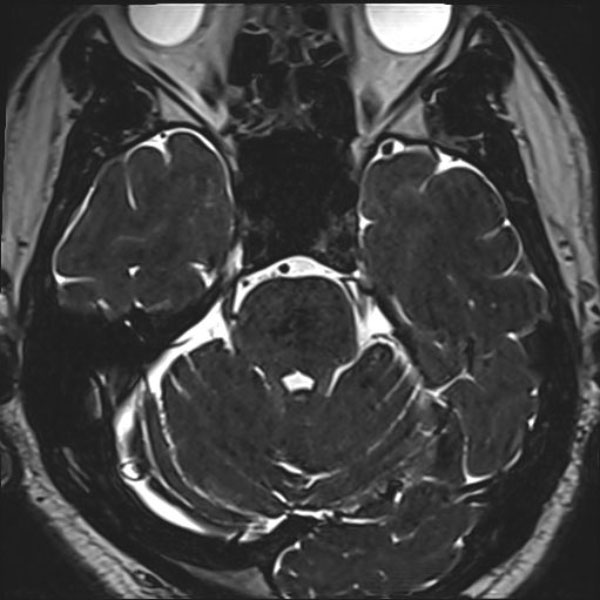

手術前

(MR1)